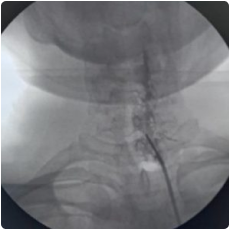

Cervical Facet injection is done under aseptic precautions in an operation theatre, under the guidance of fluoroscopy.

image 909

Intraop fluoroscopy image of cervical spine